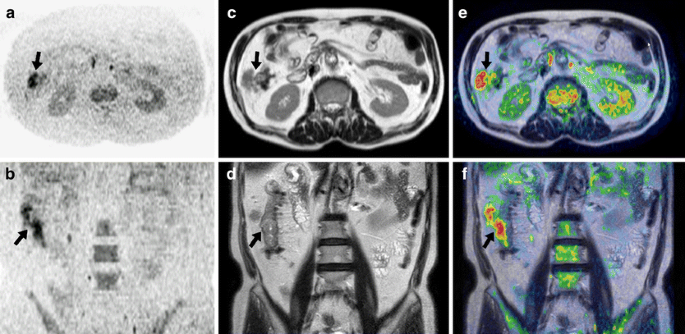

Fig. 10

Comparison of pre- and post-chemotherapy FDG-PET and DWIBS images in a 44-year-old man with diffuse large B-cell lymphoma. a Coronal maximum intensity projection FDG-PET and b coronal maximum intensity projection DWIBS images before initiation of chemotherapy. Both images show cervical, bilateral supra/infraclavicular, mediastinal, left axillary, para-aortic lymph node, and splenic involvement (arrows), and cardiac involvement (dashed arrow). c FDG-PET and d DWIBS images at the end of treatment show resolvement of all pre-existing lesions. a, b A limitation of DWIBS is that discrimination between normal and metastatic lymph nodes is still based on size criteria; the FDG-PET positive left cervical lymph node (arrowhead 1) cannot conclusively be identified as malignant on DWIBS (arrowhead 1). DWIBS also shows prominent bilateral inguinal lymph nodes (encircled) which are normal according to FDG-PET. On the other hand, thanks to its higher spatial resolution, DWIBS visualizes two separate cardiac lesions (dashed arrow), whereas FDG-PET shows only one large cardiac lesion (dashed arrow). DWIBS also allows better evaluation of the urinary tract than FDG-PET, where potential lesions can be obscured because of FDG accumulation (arrowheads 2). c Note the physiological FDG uptake in the large intestine (arrow), which should not be confused with persistent malignant lymphoma